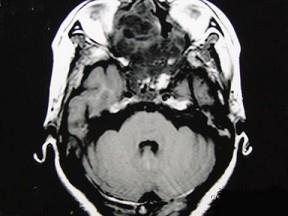

女性,41岁,鼻腔流脓涕3年,鼻部面部肿胀1年,近来加重,MRI检查如图,请选择最可能诊断 ( )